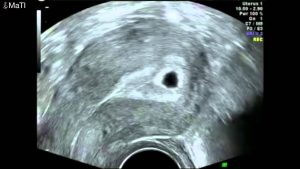

Home » Kehamilan » USG 5 Minggu Apakah Sudah Terlihat Janin Atau Kantong Kehamilan ? » USG 5 Minggu Apakah Sudah TerlihatUSG 5 Minggu Apakah Sudah Terlihat√ Scientific Base Pass quality & scientific checked by advisor, read our quality control guidelance for more info Post author Scientific review by : Redaksi Hamil.co.id fbWhatsappTwitterLinkedIn